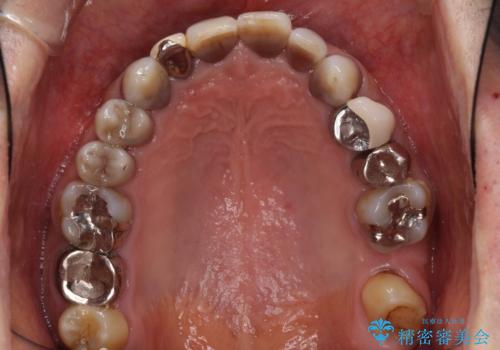

- 前歯のクロスバイトを気にして来院された患者様です。

骨格的に下顎が前方位ではありますが、歯並びが改善されれば正常咬合となることが分かったため、インビザラインを用いて咬み合わせを改善していくこととしました。